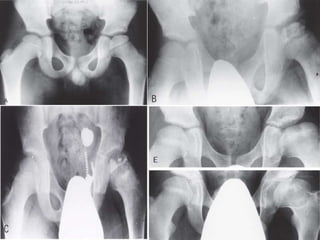

Radiographs :

• Early

 Joint space widening (

due to hypertrophy of the

articular cartilage )

 Increased density of

femoral epiphysis ( due

to loss of vascularity )

 Subcondral fracture (

salter’s sign or crescent

sign ) seen on lateral

radiograph ( signifies

beginning of collapse .

• Midstage

 Fragmentation and

flattening of head

 Widening of physis

 Femoral neck cysts

(appears as a result of

metaphyseal changes as

the part of disease

process )

 Extrusion of the femoral

head (due to flattening of

the head and increase in

medial space )

Late

 Coxa magna

 High riding trochanter ( as

a result of retarded growth

in the capital physes )

 Flattened femoral head

 Irregular articular surface

 Bi-compartmentalization of

acetabulum ( secondary

remodeling of the

acetabulum over the

flattened and subluxed

femoral head )

Waldenstrom staging

Stage Characteristics

1 Avascular stage Joint space widened (waldenstron sign )

Lateralisation of femoral head

Femoral head appears slightly denser than normal and slightly

falttened

2 Stage of resorption

(Fragmentation )

Femoral head breaks up into fragments

Lucent areas appears in the femoral head

Increased density resolves

Acetabular contour is more irregular

3. Stage of reossification The femoral head is rebuilt

New bone formation occurs in the femoral head

4. Healing stage End stage with or without defect healing